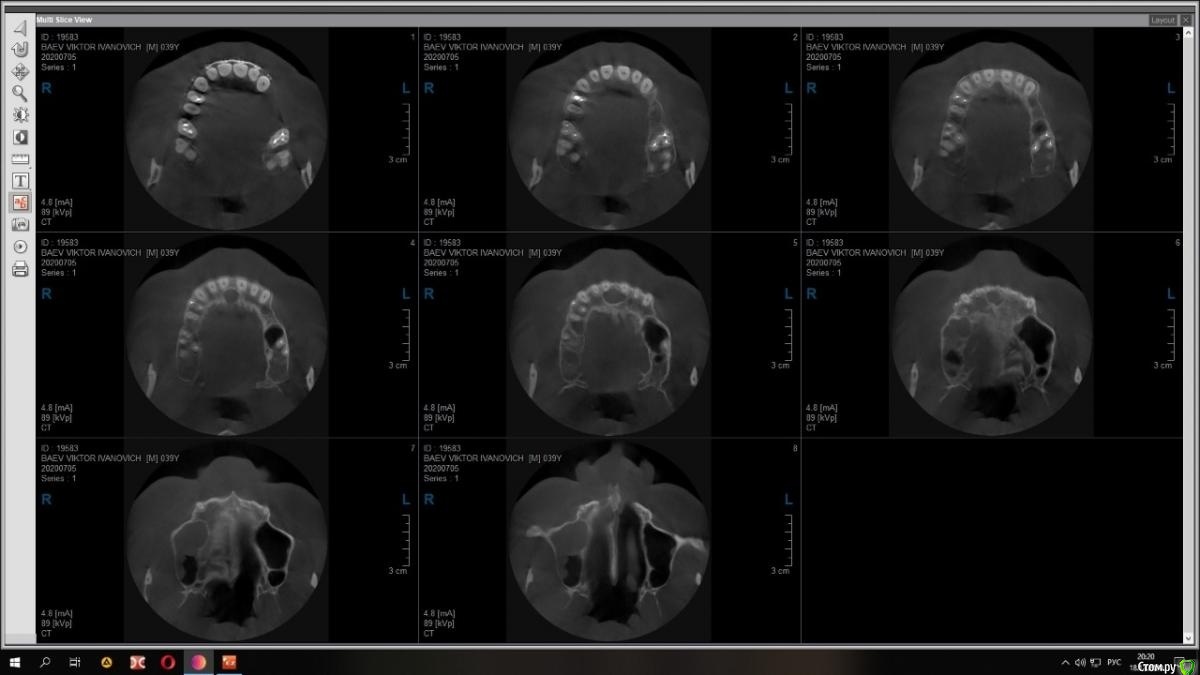

Raystom Опубликовано 15 декабря, 2020 Поделиться Опубликовано 15 декабря, 2020 Случайно на КТ перед имплантацией 36 обнаружили образование. Похоже на кисту резцового канала. Срезы снимка прилагаются.Варианты решения:1. Стационар и ЛОР, т.к. судя по снимку она, на мой взгляд, состоит из 2х частей и есть очень большая вероятность прорастания в носовой ход2. Убирать самостоятельно, но тут возникает очень много вопросов. С нёба доступ самый простой, но потом непонятно как закрыть костный дефект так, чтобы была возможность восстановления кости. При вестибулярном доступе предварительно придется делать эндо 111 с последующей резекцией, но, непонятно, удастся ли его вообще сохранить. Ещё момент, если убрать только обширную часть (нижний компонент), положить резорбируемую мембрану на дно, а аугментат через 2 месяца, дабы не пророс. При этом верхний компонент убрать с помощью ЛОР-эндоскопии.И организационный вопрос, как будет лучше, как и планировалось провести имплантацию 36, дать человеку отдохнуть на новогодних праздниках, а после уже лечение по поводу кисты Ссылка на комментарий

wladdX Опубликовано 16 декабря, 2020 Поделиться Опубликовано 16 декабря, 2020 Работайте, как планировали с 36, кисту резцового канала прооперировать можно позже (и значительно). В данном случае, как мне кажется, следует использовать нёбный доступ.Да, и другие срезы приложите, пожалуйста. 1 Ссылка на комментарий

Bier Опубликовано 16 декабря, 2020 Поделиться Опубликовано 16 декабря, 2020 Киста то малюсенькая. Вскрыть и почистить. Нёбно конечно же. Можно положить мембрану, в полость ничего не класть. В нос я бы вообще пока не лез. 1 Ссылка на комментарий

Raystom Опубликовано 21 декабря, 2020 Автор Поделиться Опубликовано 21 декабря, 2020 Киста то малюсенькая. Вскрыть и почистить. Нёбно конечно же. Можно положить мембрану, в полость ничего не класть. В нос я бы вообще пока не лез. меня смущает 3 момента, первый это то, что она прилетит рядом с апикальной частью 11, второй это то, что мне показалось она состоит из 2х частей и третье, это то, что она около 1см в диаметре (просто пока она не выросла и натворила дел, с ней можно что-то сделать) плюс ко всему стоят брекеты и мне кажется это может ускорить процесс роста кисты Ссылка на комментарий

Александр07 Опубликовано 27 декабря, 2020 Поделиться Опубликовано 27 декабря, 2020 Я бы убрал ее небно и зуб пока не трогал , наблюдал , через 6 мес повтор кт Ссылка на комментарий